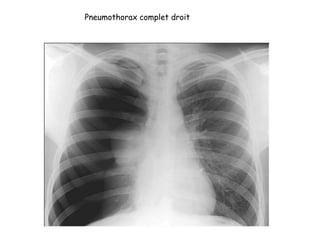

Pneumothorax complet droit